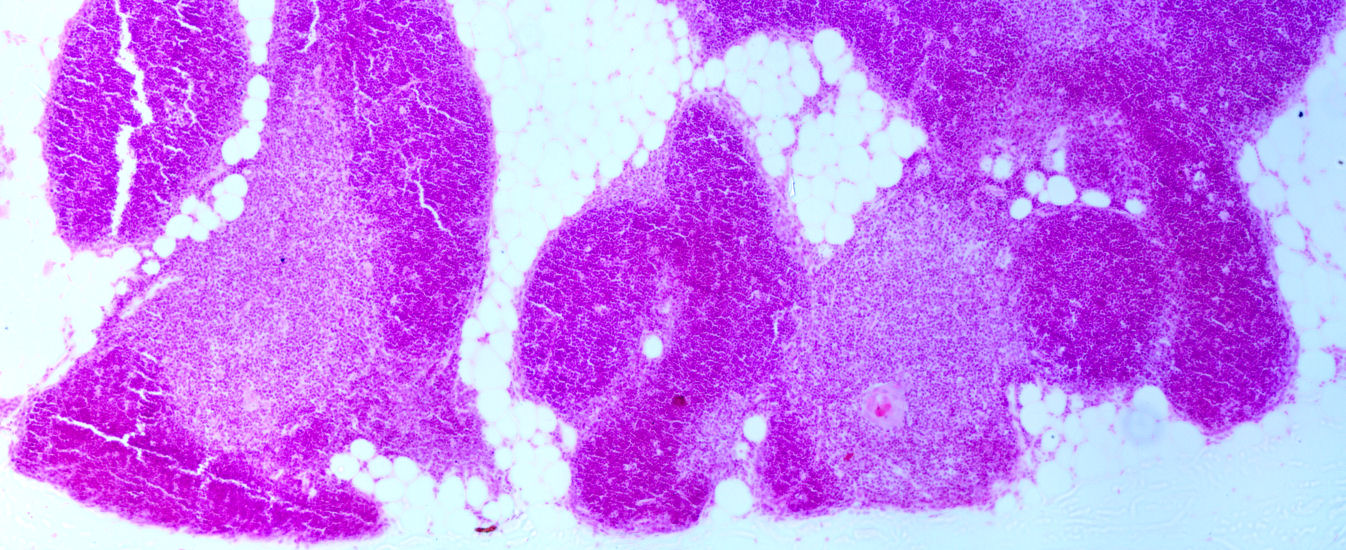

Thymus |

MicroscopeThymusThymus Higher magnification of the thymus Detail of the thymus Detail of the thymus Detail of the thymus Detail of the thymus Detail of the thymus Thymic medulla with Hassal corpuscle Detail of the thymus Detail of the thymus Detail of the thymus Detail of the thymus Detail of the thymus Other (construction area)Identify lymphocytes and epithelioreticulocytes.

Hassall body 1 (click for large)

Hassall body 2 (click for large)

The thymus 1

The thymus 2